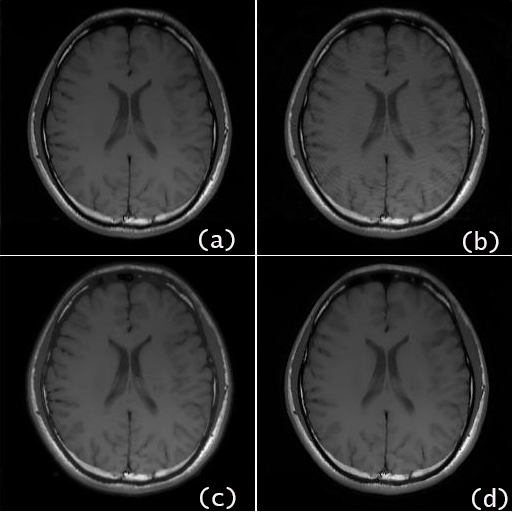

For the brain data set, the reconstructed images by the proposed algorithm using undersampled -space data of nominal reduction factor, and higher and are shown in Fig.2 (b), (c) and (d), respectively, in comparison with the SOS image using the full space data in Fig.2 (a). For the brain date set of , Fig.3 presents the reconstructed image by the proposed method in comparison with that by other recent algorithms, which are IRGN-TGV [7], SPIRiT [4] and Sparse-BLIP [8]. To provide more detailed reconstruction information for comparison, a selected area of each reconstructed image by different algorithms is zoomed and displayed in Fig. 4.

The NMSEs of the reconstructed brain images of different algorithms are listed in Table I for , respectively. The results clearly show that the proposed convex optimization method outperforms other methods in terms of the reconstruction accuracy at high undersampling rates as well as reduction of artifacts.